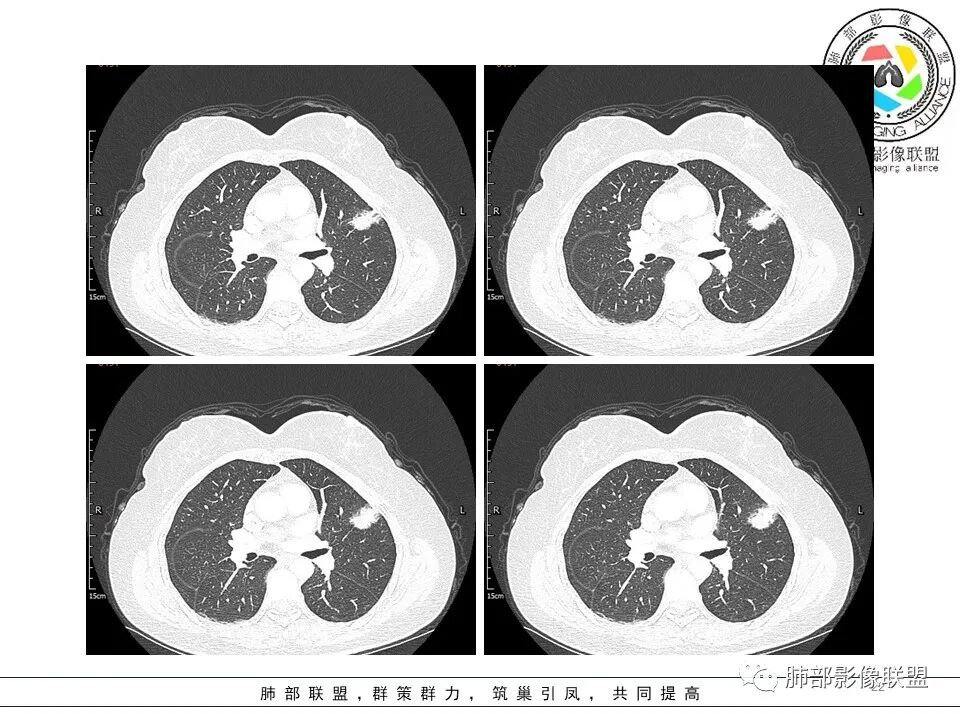

二.关于胸膜下小结节:

结节影太小,尚未能够充分反映出影像学特征。随访观察应当是恰当的处置方式。

左肺上叶近胸膜下磨玻璃小结节,考虑早期腺癌,大结节感觉密度混杂,考虑良性感染

短毛刺,空泡蜂窝,肺腺癌,靠近胸膜结节太小,性质待定。